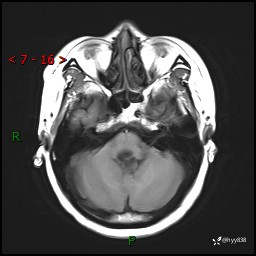

病例中年女性,头晕1年余。看看什么是软,什么是见缝钻---结果公布~

性别:女

年龄:47岁

简要病史:头晕1年余,间断恶心不伴呕吐

颅脑MRI平扫+DWI